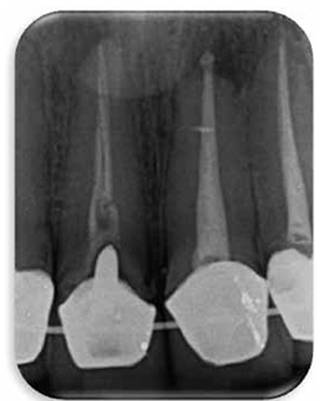

Paciente masculino de 36 años de edad sin antecedentes patológicos personales (A.P.P.) se presenta al Postgrado de Endodoncia de la Universidad Latina de Costa Rica por motivo de Trauma Dental debido un accidente laboral, el hecho ocurrió tres días anterior a su visita al centro de atención. Clínicamente se observa inflamación y un grado de movilidad II. Desalojo incisal y fuera de oclusión. (Figur 3) Radiográficamente se observa una obturación deficiente del conducto y a la vez una aparente fractura radicular. (Figura 4)

Figura 4: Radiografía inicial